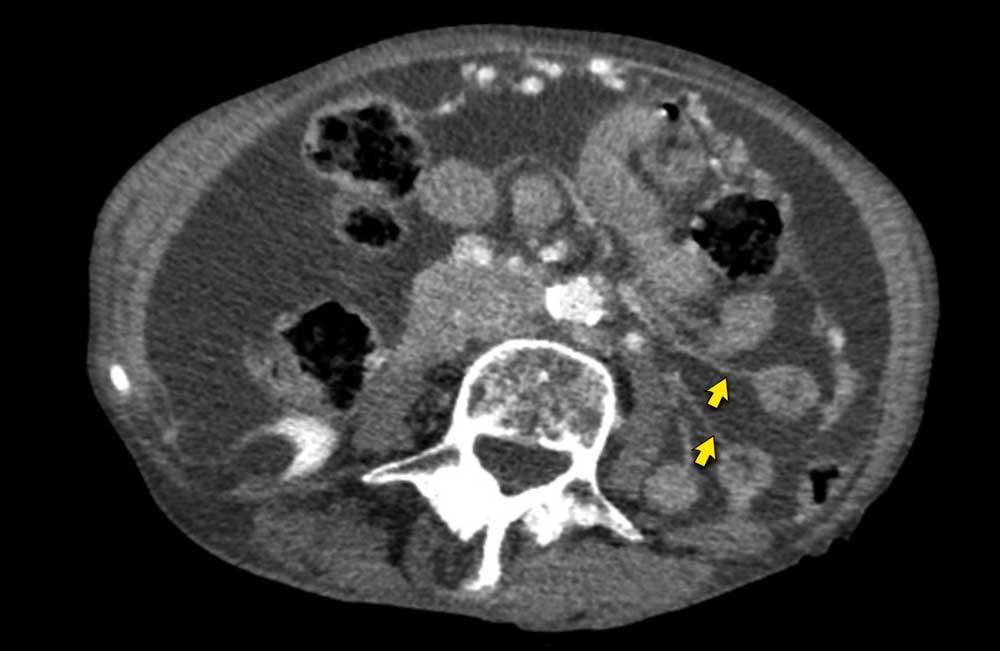

Hình ảnh

Hình ảnh CT của một bệnh nhân ung thư phúc mạc.

Một lượng nhỏ dịch cổ trướng hiện diện ở góc phần tư trước bên phải.

Các đường dày dạng nốt vuông góc với thành ruột được ghi nhận.

Hình ảnh này đại diện cho tổn thương xâm lấn mạc treo ruột lan rộng (mũi tên).